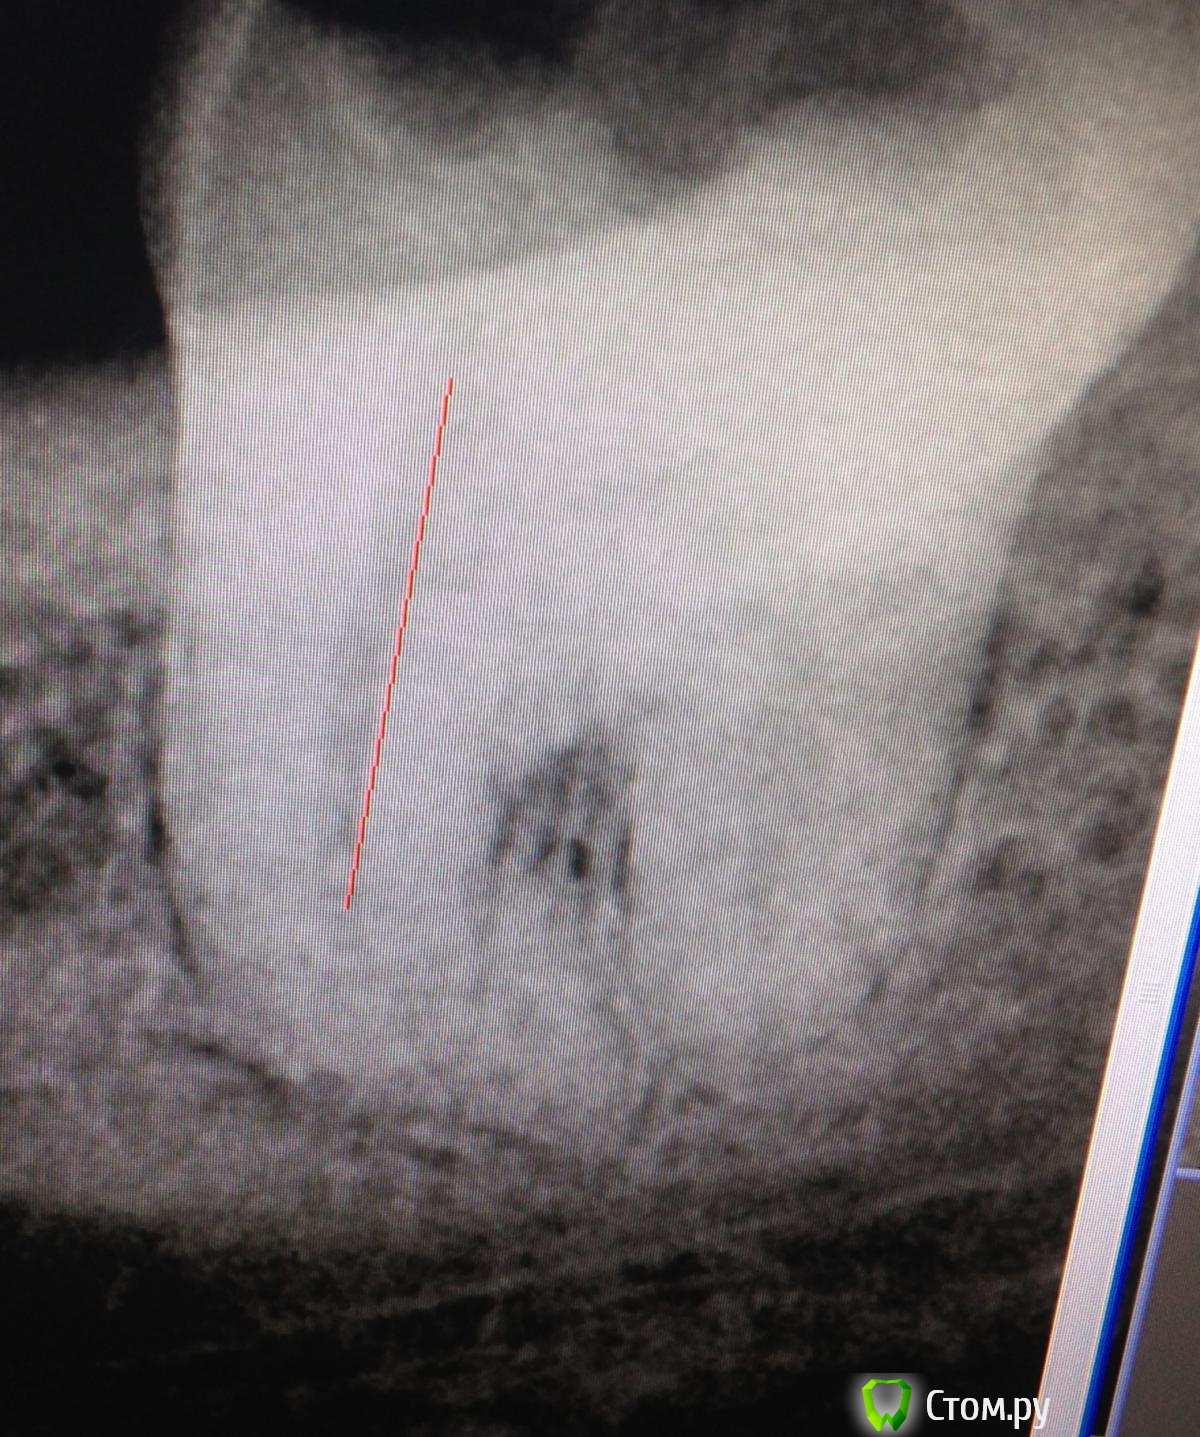

SSTi Опубликовано 5 мая, 2014 Автор Поделиться Опубликовано 5 мая, 2014 38. Пульпитный. Медиальные сходятся. Забавная кривулька вышла. ))))Латералка 2 Ссылка на комментарий

Shaid Опубликовано 5 мая, 2014 Поделиться Опубликовано 5 мая, 2014 В дистальном без петенси? Такое ощущение, что последние 2 мм остались недопакованными и апекс "зияет". Ссылка на комментарий

SSTi Опубликовано 5 мая, 2014 Автор Поделиться Опубликовано 5 мая, 2014 Да вот сижу смотрю сейчас и тоже так кажется. Хотя все по локатору ок было. И упор четкий. 16 мм рабочая в дистальном. 16.5 уже пищал , что вышел за апекс. Ссылка на комментарий